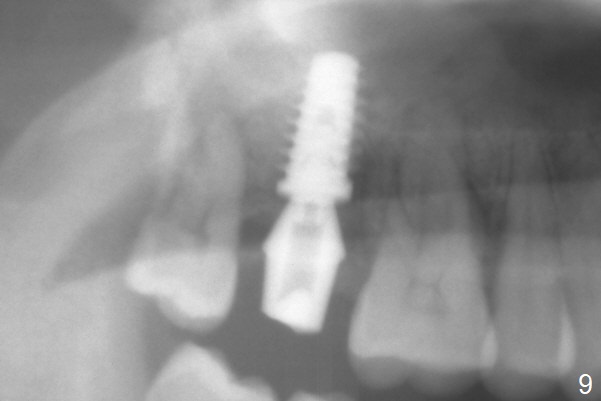

When the 59-year-old man returns for #24 implant placement, the tooth #2 is found to have crack (Fig.1,2 arrowheads), associated with buccal and palatal fistulae (*) and loss of amalgam (Fig.4 *). Abundant granulation tissue is attached to the roots of the affected tooth (Fig.3), indicating severe bone loss. There is a plateau associated with the septum and buccal sockets, which is the site of osteotomy. Magic split and 3 and 3.8 mm Magic Expanders are used to initiate osteotomy. After use of 4.3 mm Magic Drill for about 3 mm, Osteogen plug and allograft are used for sinus lift, followed by insertion of a 4.5x11 mm dummy implant (Fig.5). When a 5.5x9 mm dummy implant is placed with stability, it appears to be seated cervical (Fig.6,7). When a 6x9 mm IBS implant (definitive) is placed with a 6.5x5.5(4) mm abutment, they are seated too deep for provisional (Fig.8). The implant/abutment are removed and replaced by a 6.5x11 mm one in a shallower position; after trimming the same abutment as mentioned above (Fig.9), an immediate provisional is fabricated to keep bone graft in place. Fabrication of Tap with soft tissue markers will reduce the chance of miscalculation and waste of implants. The coronal threads of the implant are covered with bone 6 months postop (Fig.10). One month later when a permanent crown tries in, the implant is found to be loose and tender. A healing abutment is placed. Six months later, the patient returns for crown retry-in. The tooth #1 seems to have shifted mesially (Fig.11 arrow). When the abutment is placed, the implant remains tender and loose. After implant removal with a wrench, there is no granulation tissue or bony defect, including the intact sinus floor (Fig.12 <). Since the tooth #1 has deep periodontal pockets and mobility, the tooth is extracted with abundant granulation tissue. After debridement, Osteogen plug is placed in the socket of #1, while Vanilla graft is placed at the site of #2 (Fig.13 *). Three weeks later, the socket of #2 heals with exposure of Osteogen plug (Fig.14 (B: buccal)).